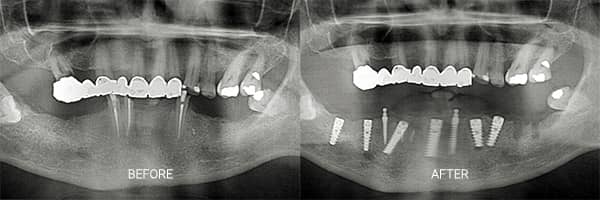

Mini Dental Implants Before and Afters

Check out our patients before and afters. Most treatments are provided on two trips of seven days stay in Agadir. Affordable mini dental implants without compromise.

We would have to see an X-ray to determine this for certain. In these cases, some bone grafting and the membrane are usually required.